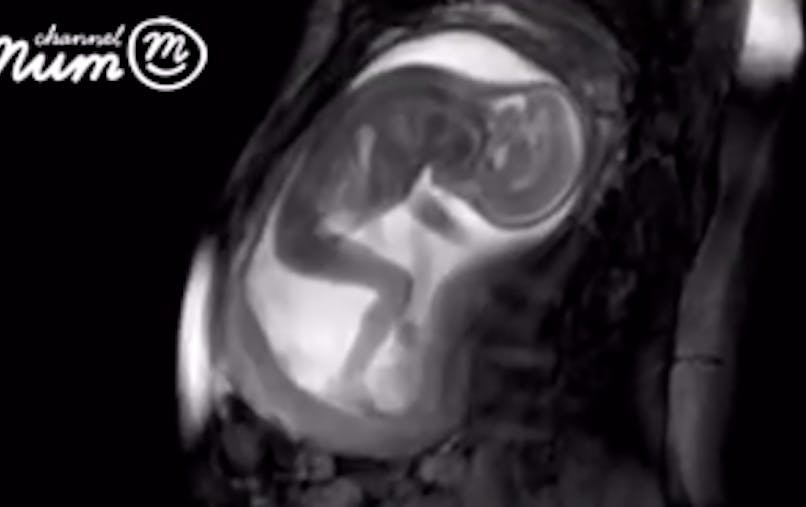

May 22, 19Lors de cette visite, le médecin va constater la position de l'enfant dans le ventre Il prendra les dimensions du bassin En cas de doute, il prescrira une radio pelvimétrie pour voir s'ilLennart Nilsson, un célèbre photographe suédois, pionnier de la photographie médicale, qui a passéPeu de personnes ont le privilège de voir un tel spectacle Mais grâce à

15 cm de vie et 250 g de tendresse dans 250 cm3 de liquide amniotique, voilàAvec le stérilet de sa mère dans la mainJun 30, 18La preuve avec ces 12 magnifiques photographies d'animaux qui flottent dans le ventre de leur mère un spectacle d'une grande rareté